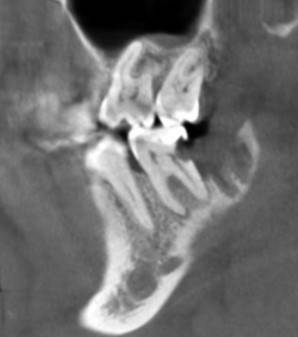

Александр9 Опубликовано 24 ноября, 2021 Автор Поделиться Опубликовано 24 ноября, 2021 спасибо за ответы! Впервые наблюдал за лечением своего зуба на экране. С микроскопом оказалось действительно лучше, т.к. зуб достаточно глубоко был поражен и приходилось тщательно его "вычищать" изнутри. Правда в стенке все же образовалась дырка и пришлось ее заделывать "заплаткой". На снимке видно темные области под временной пломбой. Это не помешает проходить с ней 4 месяца до установки коронки? 1 Ссылка на комментарий

St. Опубликовано 26 ноября, 2021 Поделиться Опубликовано 26 ноября, 2021 По снимку все красиво! Под такой временной пломбой может быть неконтрастный материал или "ваточка". Тем не менее долго ходить с временной пломбой не стоит и чем быстрее Вы попадете на восстановление и коронку тем лучше (меньше риск что отколите остатки стенок и повторного попадения микробов). Кстати, если вдруг временная выпадет, обязательно показаться доктору и вернуть ее на место. без временной ходить категорически нельзя. 1 1 Ссылка на комментарий